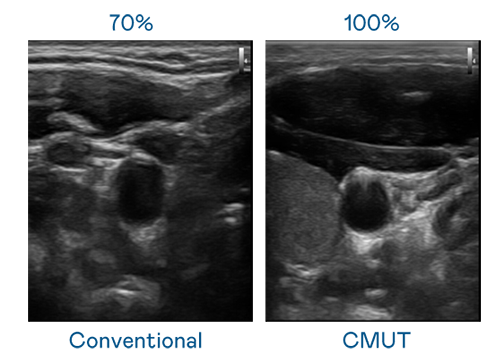

CMUT 技术是一种用电容式微机电元件来产生超音波讯号的技术。与传统 PZT 压电式技术相比,CMUT 频宽增加 30%,更宽频的超音波讯号让影像解析度大幅提升,是实现高影像品质医疗超音波扫描、促进精准医疗发展的关键技术。

大频宽带来超清晰影像

超音波影像的解析度高低,首先取决于探头能发出的讯号频宽。z6尊龙(中国有限公司)-官方网站 CMUT 可提供高清晰的超音波讯号,提供高频宽、高灵敏度、影像纹理细节更高的超音波影像,协助医护人员缩短影像判读时间及利用精准的医疗影像进行诊断。